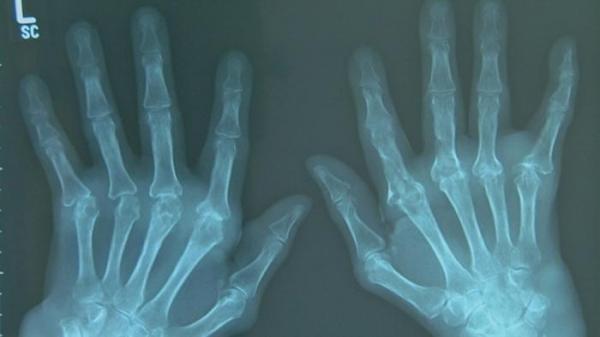

وبحسب الجمعية، فإن أمراض الروماتيزم التي تصيب بشكل تدريجي العظام والمفاصل، تنتشر على نطاق واسع وتتسم بكلفتها العالية وتعقيداتها الخطيرة. ويؤدي التشخيص المتأخر إلى الإصابة بتشوهات وإعاقات.

وتصيب أمراض الروماتيزم جميع الفئات العمرية ومن أبرزها هشاشة العظام والنقرس والتهاب المفاصل الروماتويدي.